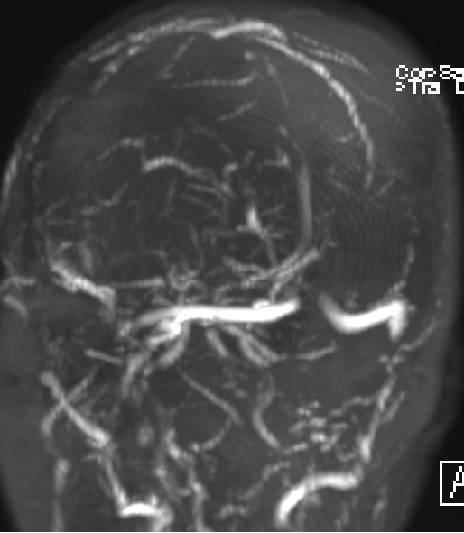

2015-1-30 DSA